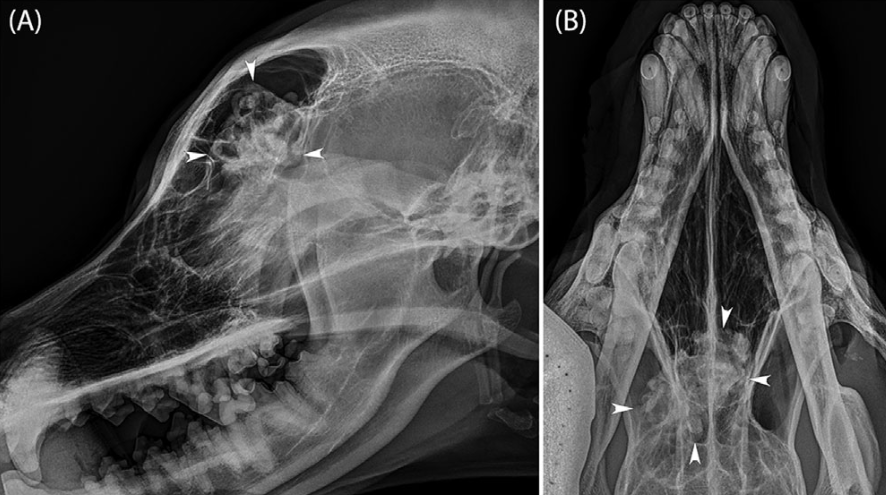

지역병원에서 볼때는

방사선 검사상 이정도 영상으로 보일 수 있다.

명확한 골밀도 변화 양상이 보이는것을 확인할 수 있을것이다.